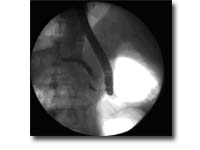

ERCP及EST技术

ERCP是将十二指肠镜经口插入十二指肠,寻找十二指肠乳头,再经活检通道置入造影导管并插入乳头,在X线透视下注入造影剂显示胆管、胰管的形态及异常变化。ERCP是胆道和胰腺疾病最为有效的诊断技术之一,也是胆胰疾病内镜下介入治疗的基础。包括:急性化脓性胆管炎、急性胆源性胰腺炎、胆总管结石、胆道蛔虫、梗阻性黄疸术前引流、胆瘘、胰瘘、慢性胰腺炎等。